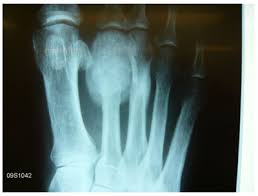

What Does Bone Cancer Of The Foot Look Like / Chondrosarcoma Of The Distal Phalanx Of The Right Great Toe Report Of A Rare Malignancy And Review Of Literature Mondal Sk J Can Res Ther / This is the most common type, but not the most dangerous type of skin cancer of the foot, toe and ankle.

A skull consists of the frontal, temporal, parietal and occipital bones. This type of cancer usually does not spread deep, except when allowed to progress for a. The pain can sometimes be wrongly mistaken for arthritis in adults and growing pains in children and teenagers. Although rare, bone tumors can occur in the foot and ankle. Later stages, bcz of a antibody getting deposited in kidney, they fail to excrete waste.now we will have kidney failure symptoms like swelling of legs,puffiness of face, altered urine output and.